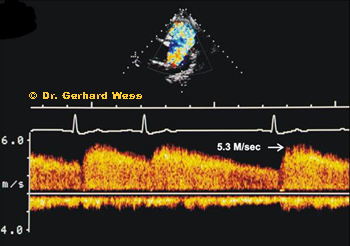

CW Doppler image in PDA Continuous-wave Doppler helps estimate the velocity through the PDA and assess whether pulmonary hypertension may already be developing.